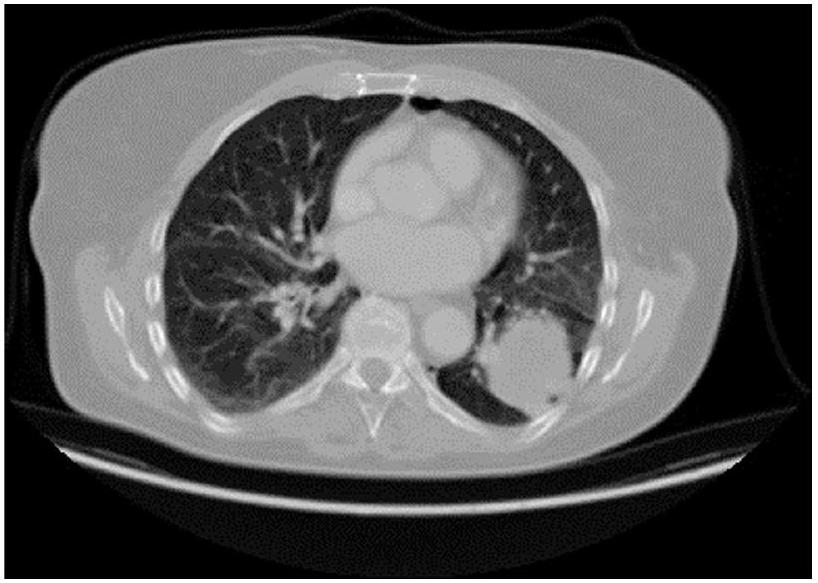

مجموعة البيانات

لهذه الدراسة، تم استخدام مجموعة بيانات سرطان الرئة من مستشفى العراق التعليمي للأورام/المركز الوطني لأمراض السرطان (IQ-OTH/NCCD)، المتاحة للجمهور على كاجل.

، تم استخدامه. نُشر في عام 2019، تتضمن هذه المجموعة من البيانات صور الأشعة المقطعية من 110 أفراد تم تشخيصهم بسرطان الرئة، تشمل مراحل مختلفة: حميدة، خبيثة، وطبيعية. المشاركون من جنسيات وأعمار ومستويات تعليمية مختلفة. من بين 110 مريضًا، كان لدى 40 أورام رئوية خبيثة، و15 أورام حميدة (غير سرطانية)، و55 رئة طبيعية. قدم كل مريض حوالي

قم بمسح شرائح بسمك 1 مم.

تتكون مجموعة البيانات من 1,097 صورة مقطعية تم تنظيمها في ثلاث مجموعات متميزة وهي مجموعة الأورام الحميدة، والأورام الخبيثة، والمجموعة الطبيعية لأمراض سرطان الرئة. تحتوي فئة الأورام الحميدة على 120 صورة، بينما تمتلك فئة الأورام الخبيثة 561 صورة بالإضافة إلى 416 صورة في الفئة الطبيعية. يتم تقسيم أورام الرئة إلى أنواع حميدة غير سرطانية وأنواع خبيثة سرطانية مع تمييز إضافي بين الأورام والأورام الكتلية. مرت مجموعة البيانات بعمليات تدريب لـ